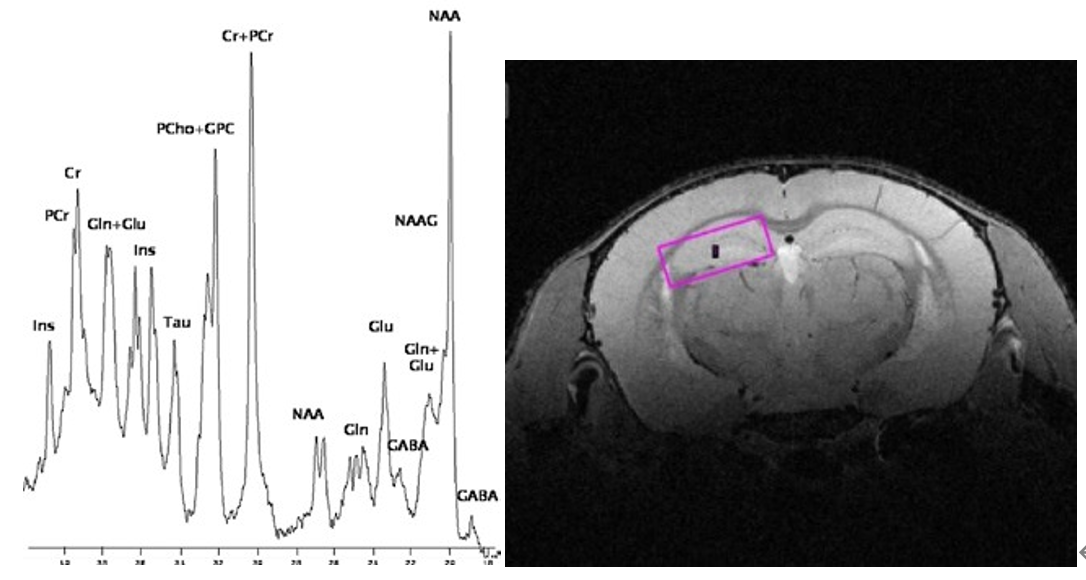

2、Localized Spectroscopy

STEAM spectrum of the mouse brain acquired using the MRI CryoProbeTM at 15.2 Tesla.

Acquisition details: STEAM, voxel size: (2 x 2 x 2) mm³, TR: 8 s, 128 averages, resolution enhancement with shifted Gauss filtering, TE: 1.1 ms, shift: 7%, broadening: 7 Hz